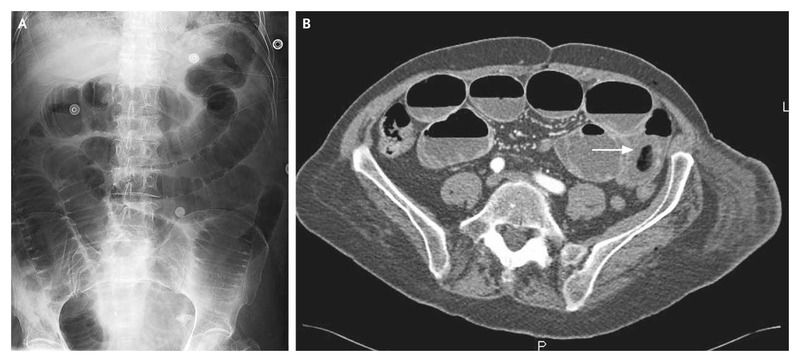

A 72-year-old woman presented with a 2-day history of abdominal pain associated with nausea and vomiting. Over the previous 10 years, she had had progressive Alzheimer’s disease, requiring her to live in a long-term care facility.

What’s the Diagnosis ?